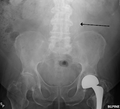

The faint outline of the calcified wall of an AAA as seen on plain X-ray

-